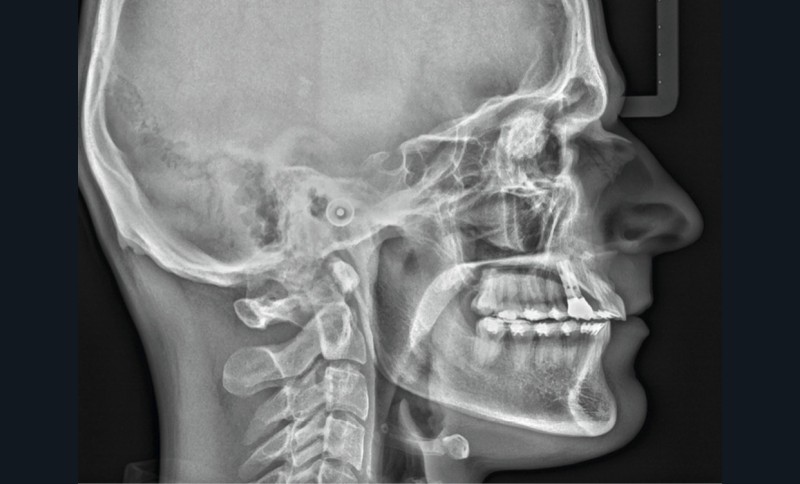

À l’examen de ces nouveaux clichés, une image radiologique de type « masse ronde » en regard des orbites se détache nettement. Immédiatement remontent mes souvenirs de cours de radio de l’examen du CECSMO. On nous apprenait à regarder la selle turcique et à reconnaître une tumeur. Une intime conviction s’impose : mon patient a une tumeur…

Je retourne immédiatement vers les premiers clichés avant traitement : l’image radiologique de la masse était déjà là !

Le volume semble identique, ce qui me rassure néanmoins sur le caractère peu évolutif. Je consulte sa fiche médicale, mais aucun problème de santé n’est mentionné.